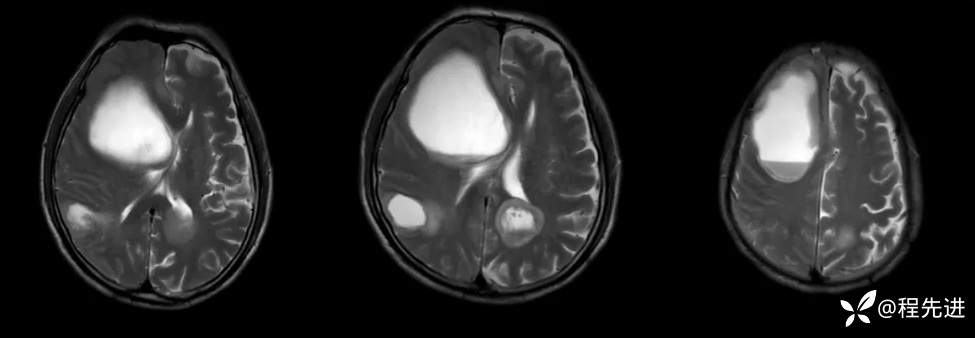

T2: